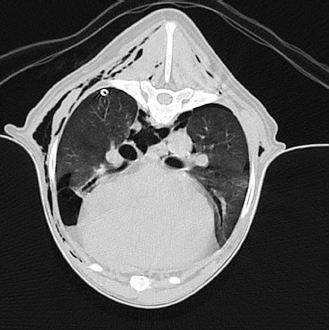

Because pneumothorax had not resolved by continuous chest drainage within 2 days computed tomography (CT) was performed with the goal to diagnose the causative factor(s) of persistent spontaneous pneumothorax as well as to propose a definitive treatment plan to the owners. General anesthesia was performed using the same protocol outlined previously. Using a 16 slice helical CT scanner (Philips Brilliance; Philips Medical Systems, Best, Netherlands) the thorax was scanned with and without intravenous contrast media (600 mg/kg i.v.; Unilux® 300 mg/ml, Sanochemia Pharmazeutika GmbH, Neufeld An Der Leitha, Germany) at a slice thickness of 2 mm and an increment of 1 mm using a high-resolution soft tissue kernel with the dog positioned in sternal recumbency Images were assessed in the transverse and reconstructed sagittal and coronal planes using a lung window (window width: 1,400 HU, window level: −400 HU).

CT imaging revealed a mild bilateral pneumothorax and a roundish radiolucent, bullous, subpleural air-filled structure at the caudo-ventral aspect of the right middle lung lobe at the level of the 6th to 7th intercostal space with a size of 1.8 × 1.8 × 1.4 cm (Fig. 3).

Additionally, a mild to moderate bilateral subcutaneous emphysema and pneumomediastinum were detected bilaterally at that level (Fig. 4). Mild to moderate atelectasis of the right middle, right caudal, and accessory lung lobe was evident in the ventral aspect of the respective lung lobes.

Fig. 4. Transverse CT-image of the thorax at the level of the 5th rip (lung window). A 1.8 × 1.8 × 1.4 cm radiolucent, bullous, air-filled structure within the caudo-ventral aspect of the right medial lung lobe is visible; the air-filled cavity is located at the periphery of the respective lung lobe and seems surrounded by a thin soft tissue dense margin. Additionally, mild bilateral pneumothorax, as well as mild to moderate pneumomediastinum and bilateral subcutaneous emphysema are visible.